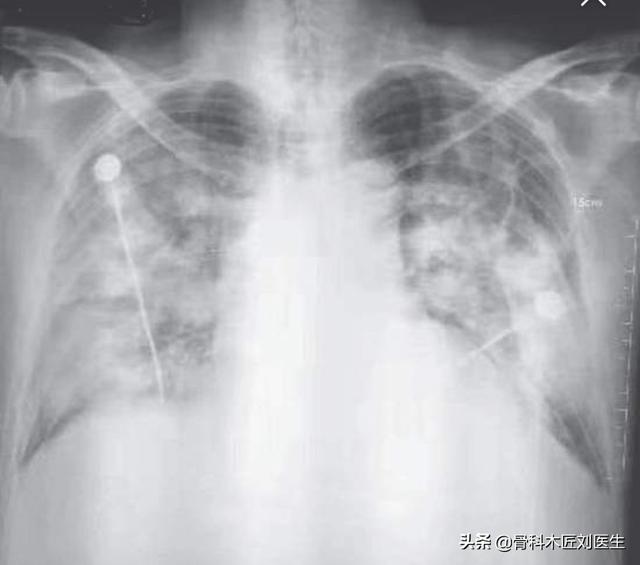

Les radiographies du thorax et l'imagerie par tomodensitométrie des poumons peuvent révéler des zones d'ombre inégales dans les poumons, qui sont évidentes dans les bandes extérieures des poumons, et dans les cas les plus graves, des zones d'ombre solides dans les poumons peuvent être observées.

Il a été traité avec des antibiotiques et s'est considérablement résorbé au bout de 9 jours :

2. avec des caractéristiques d'imagerie de pneumonie :Cela signifie qu'il y a des changements inflammatoires dans les poumons, présentant de multiples petites ombres en taches et des changements interstitiels, qui sont évidents dans les bandes externes des poumons, et même des changements tels que de multiples ombres en verre dépoli et des ombres d'infiltration dans les deux poumons. Vous vous demandez peut-être pourquoi il y a des changements d'imagerie dans les poumons après une infection. C'est principalement parce qu'une fois que le virus a envahi les poumons, il peut provoquer une congestion et un œdème dans les poumons, qui se traduisent par des ombres de haute densité sur la radiographie ou la tomodensitométrie.

②. Le thorax présente les caractéristiques d'imagerie d'une pneumonie.

Au stade initial, elle présente de multiples petites taches et des changements interstitiels, qui peuvent évoluer vers de multiples taches en verre dépoli et infiltrées dans les deux poumons et, dans les cas les plus graves, des changements solides dans les poumons peuvent se produire, ce qui donne ce que l'on appelle communément les "poumons blancs".